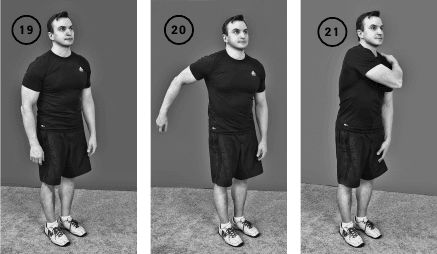

Упражнение «Замах рукой»

Исходное положение – стоя. Правое плечо свободно свисает вниз.

Раскачиваете свободно свисающее правое плечо за счет движений корпусом. И в момент максимального раскачивания забрасываете силой инерции кисть правой руки на левый плечевой сустав, после опускаете плечо вниз. Повторяете упражнение 3-10 раз. При необходимости выполняете упражнение для другой руки (ил. 19, 20, 21).

Упражнение «Замах рукой» приводит как к активному, так и к пассивному движению в плечевом суставе. Это может быть очень полезно при разработке парализованной или частично парализованной руки, например в результате инсульта. Пассивное раскачивание создает определенный объем движений, забрасывание кисти включает в работу функционирующие мышечные волокна и тренирует их.